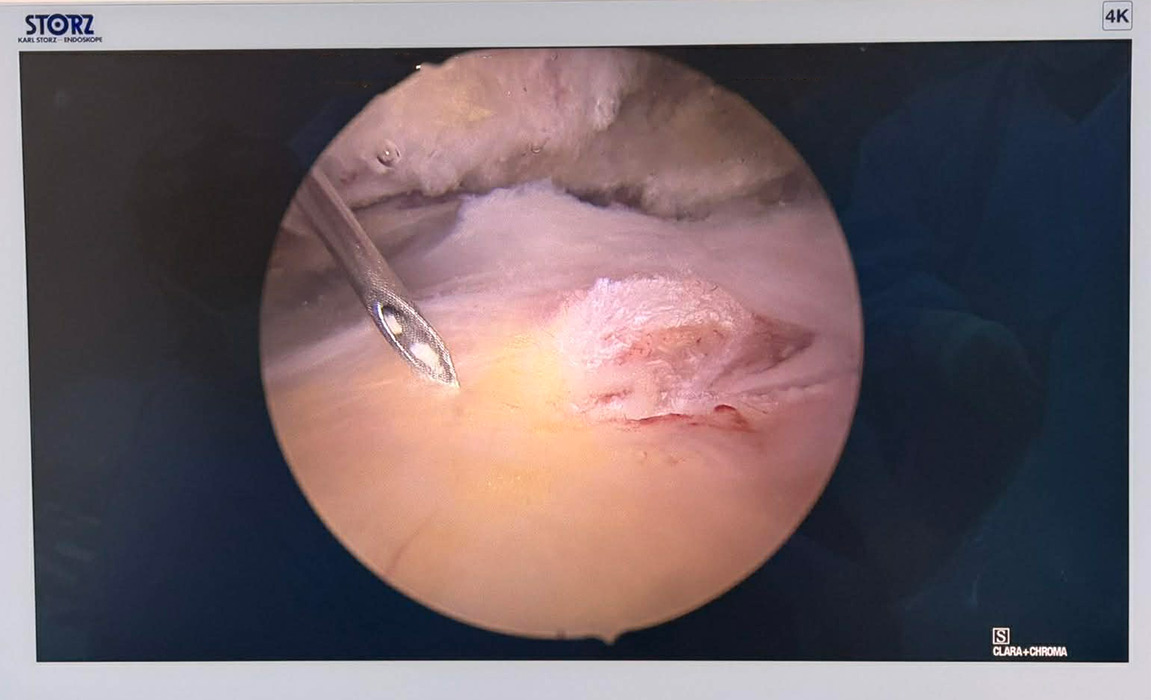

Ενδείκνυται όταν αποτύχουν όλες οι συντηρητικές μέθοδοι και πραγματοποιείται αρθροσκοπικά με μικρές οπές.

Αρθροσκόπηση ώμου σε ασθενή μας για αφαίρεση μεγάλου ασβεστώματος και συρραφή ρήξης τενόντων